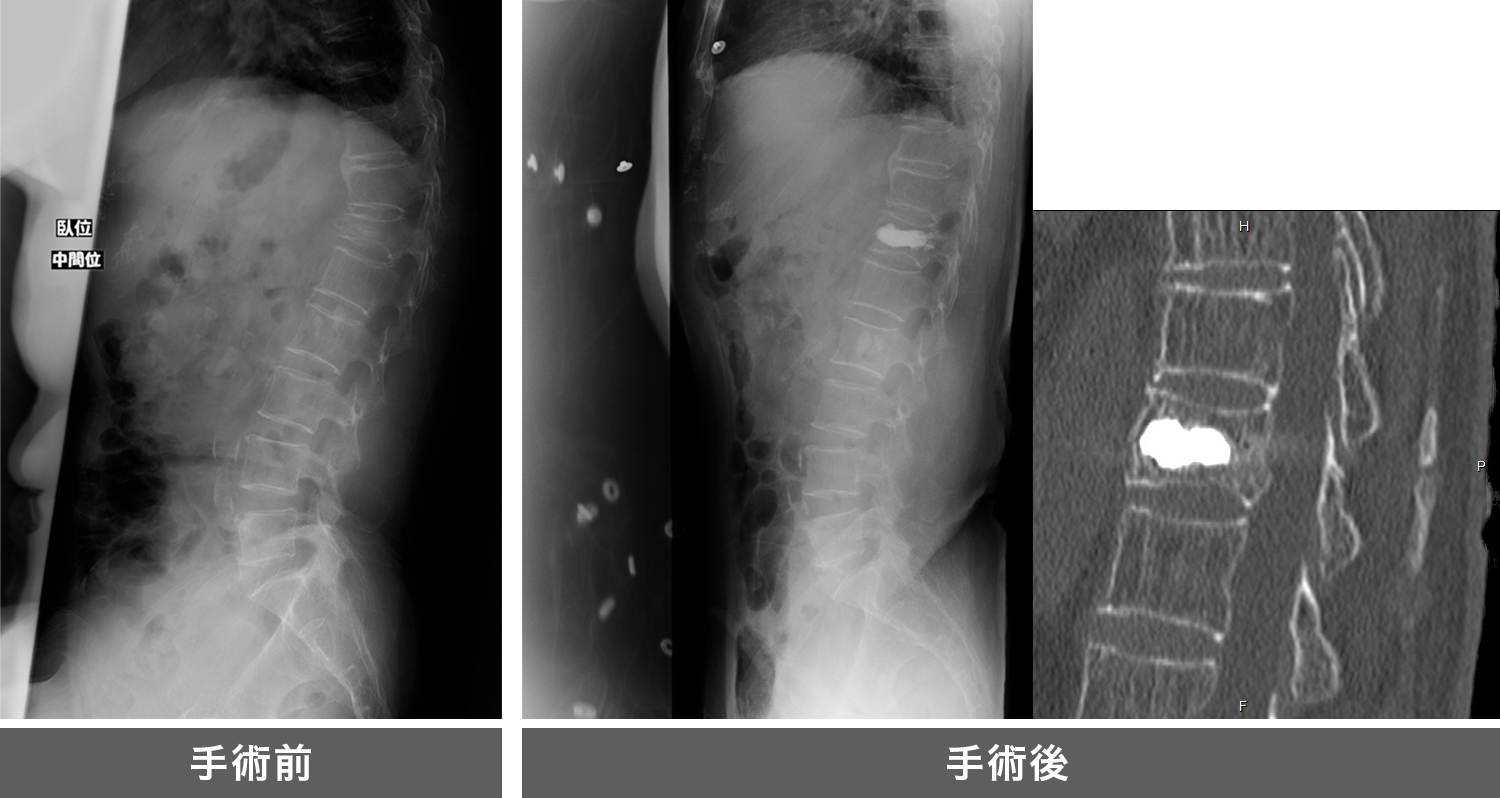

バルーンで潰れた椎体を持ち上げ、セメントを注入する手術です。

当院では平成29年度より本法を開始しており、年間25件程度の手術を施行しています。

従来は長期の安静臥床や体に負担の大きな広範囲の固定手術を余儀なくされていましたが、この手術により早期の離床が可能となる方もいます。